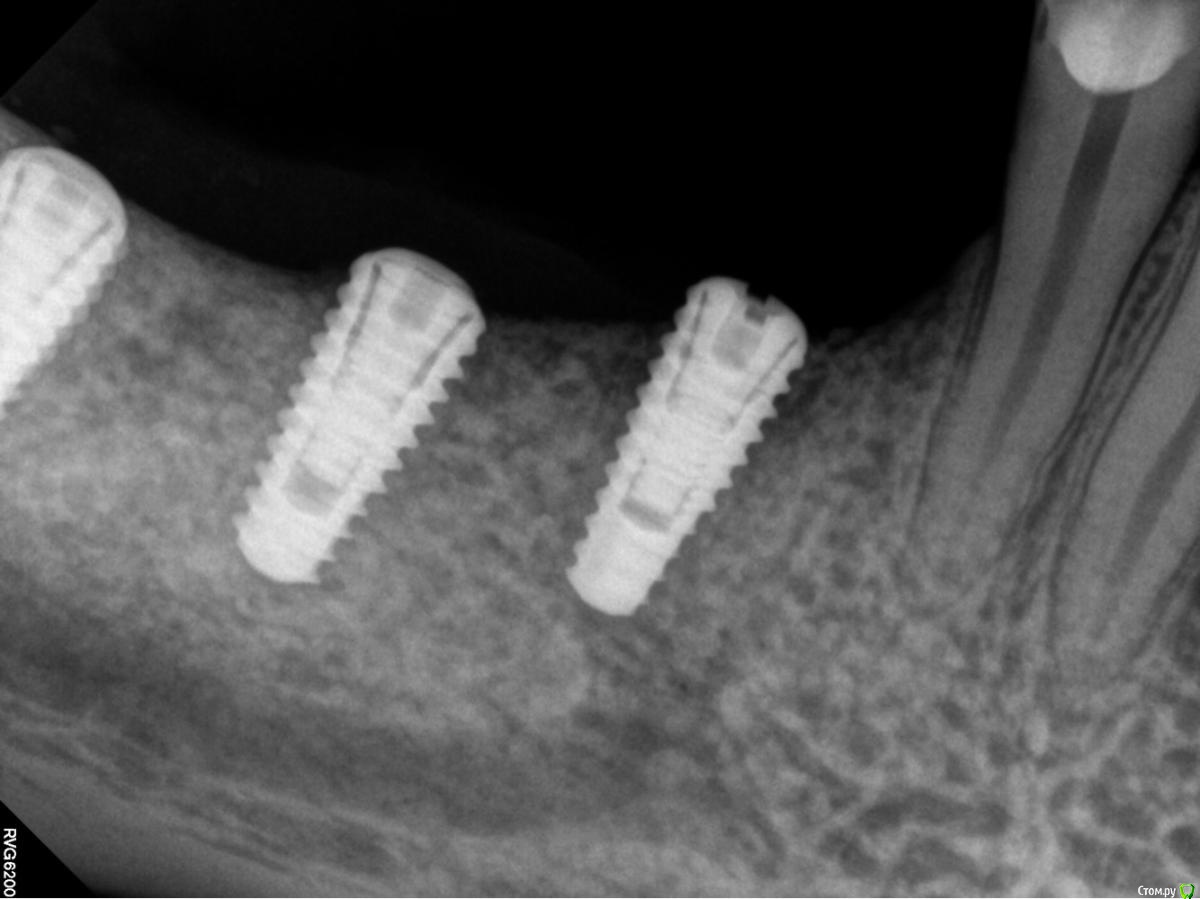

Orange1 Опубликовано 14 февраля, 2017 Поделиться Опубликовано 14 февраля, 2017 Здравствуйте коллеги.Проведена имплантация Megagen лето 2016.Ваше мнение по поводу обнажения витков.Помогите советом. Как С ними справиться.Спасибо! Ссылка на комментарий

Orange1 Опубликовано 14 февраля, 2017 Автор Поделиться Опубликовано 14 февраля, 2017 Вот такая проблема Ссылка на комментарий

Orange1 Опубликовано 15 февраля, 2017 Автор Поделиться Опубликовано 15 февраля, 2017 Согласен, если справится с ними, то шашлычек может помочь. Когда ставили, заглубили на какой уровень?Погружал на 0.5 Ссылка на комментарий

dok1 Опубликовано 15 февраля, 2017 Поделиться Опубликовано 15 февраля, 2017 Без обид. Сомнительно, что погружали. По логике погружение - это со стороны самой глубокой "стороны". Но тут проблем действительно не наблюдается особых. За шашлык + 1000. Что за система,если не секрет? Сомневаюсь в догадках. 1 Ссылка на комментарий

Orange1 Опубликовано 17 февраля, 2017 Автор Поделиться Опубликовано 17 февраля, 2017 Да я тоже сомневаюсь в полном погружении, хотя они по протоколу должны погружаться.Погружал.думаю сверхкомпрессия съела.сейчас бы делал с времянками.Вчера раскрылся.удалил 18.шашлычок на 4.5.наблюдаю жду результата.фото к сожалению не делал.спасибо за советы коллеги. Ссылка на комментарий

Orange1 Опубликовано 17 февраля, 2017 Автор Поделиться Опубликовано 17 февраля, 2017 Кстати витки просвечиваются и более апикально.торк выдерживает.как с ними в будущем кто то наблюдал? Ссылка на комментарий